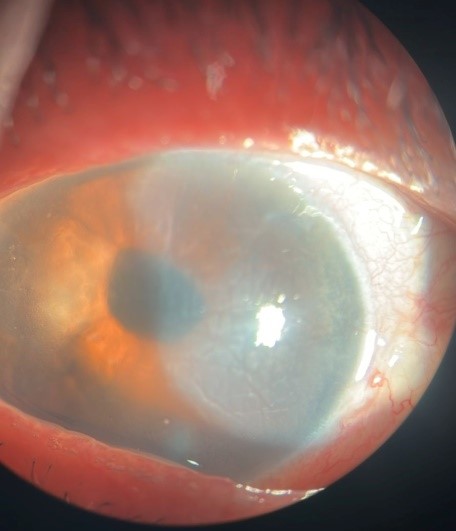

Slit-lamp examination demonstrated regression of corneal edema, with a well-centered intraocular lens and a persistent margin of edema delineating the area of DMD (Figure 3). OCT evaluation revealed partial reapplication of Descemet’s membrane with persistent stromal edema (Figure 4).

Figure 3: Slit-lamp image after 2 weeks showing regression of corneal edema localized to the nasal zone, with visible iris details and intraocular lens reflex.